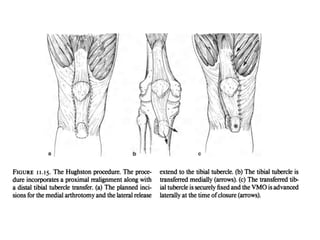

Distal Realignment Surgeries Aimsto diminish the Q angle or TT-TG distance with anteromedialisation of tibial tuberosity and unloads patello femoral articulation . Indications 1. Q angle or /1" TT-TG distance > 20mm 2. Patellar alta 3. Normal patellar glide 4. Medial facet arthritis Contraindications 1.Skeletally immature patients 2. incompetent MPFL 3. Diffuse patellar arthritis

• 78.

• 79.

• 80.